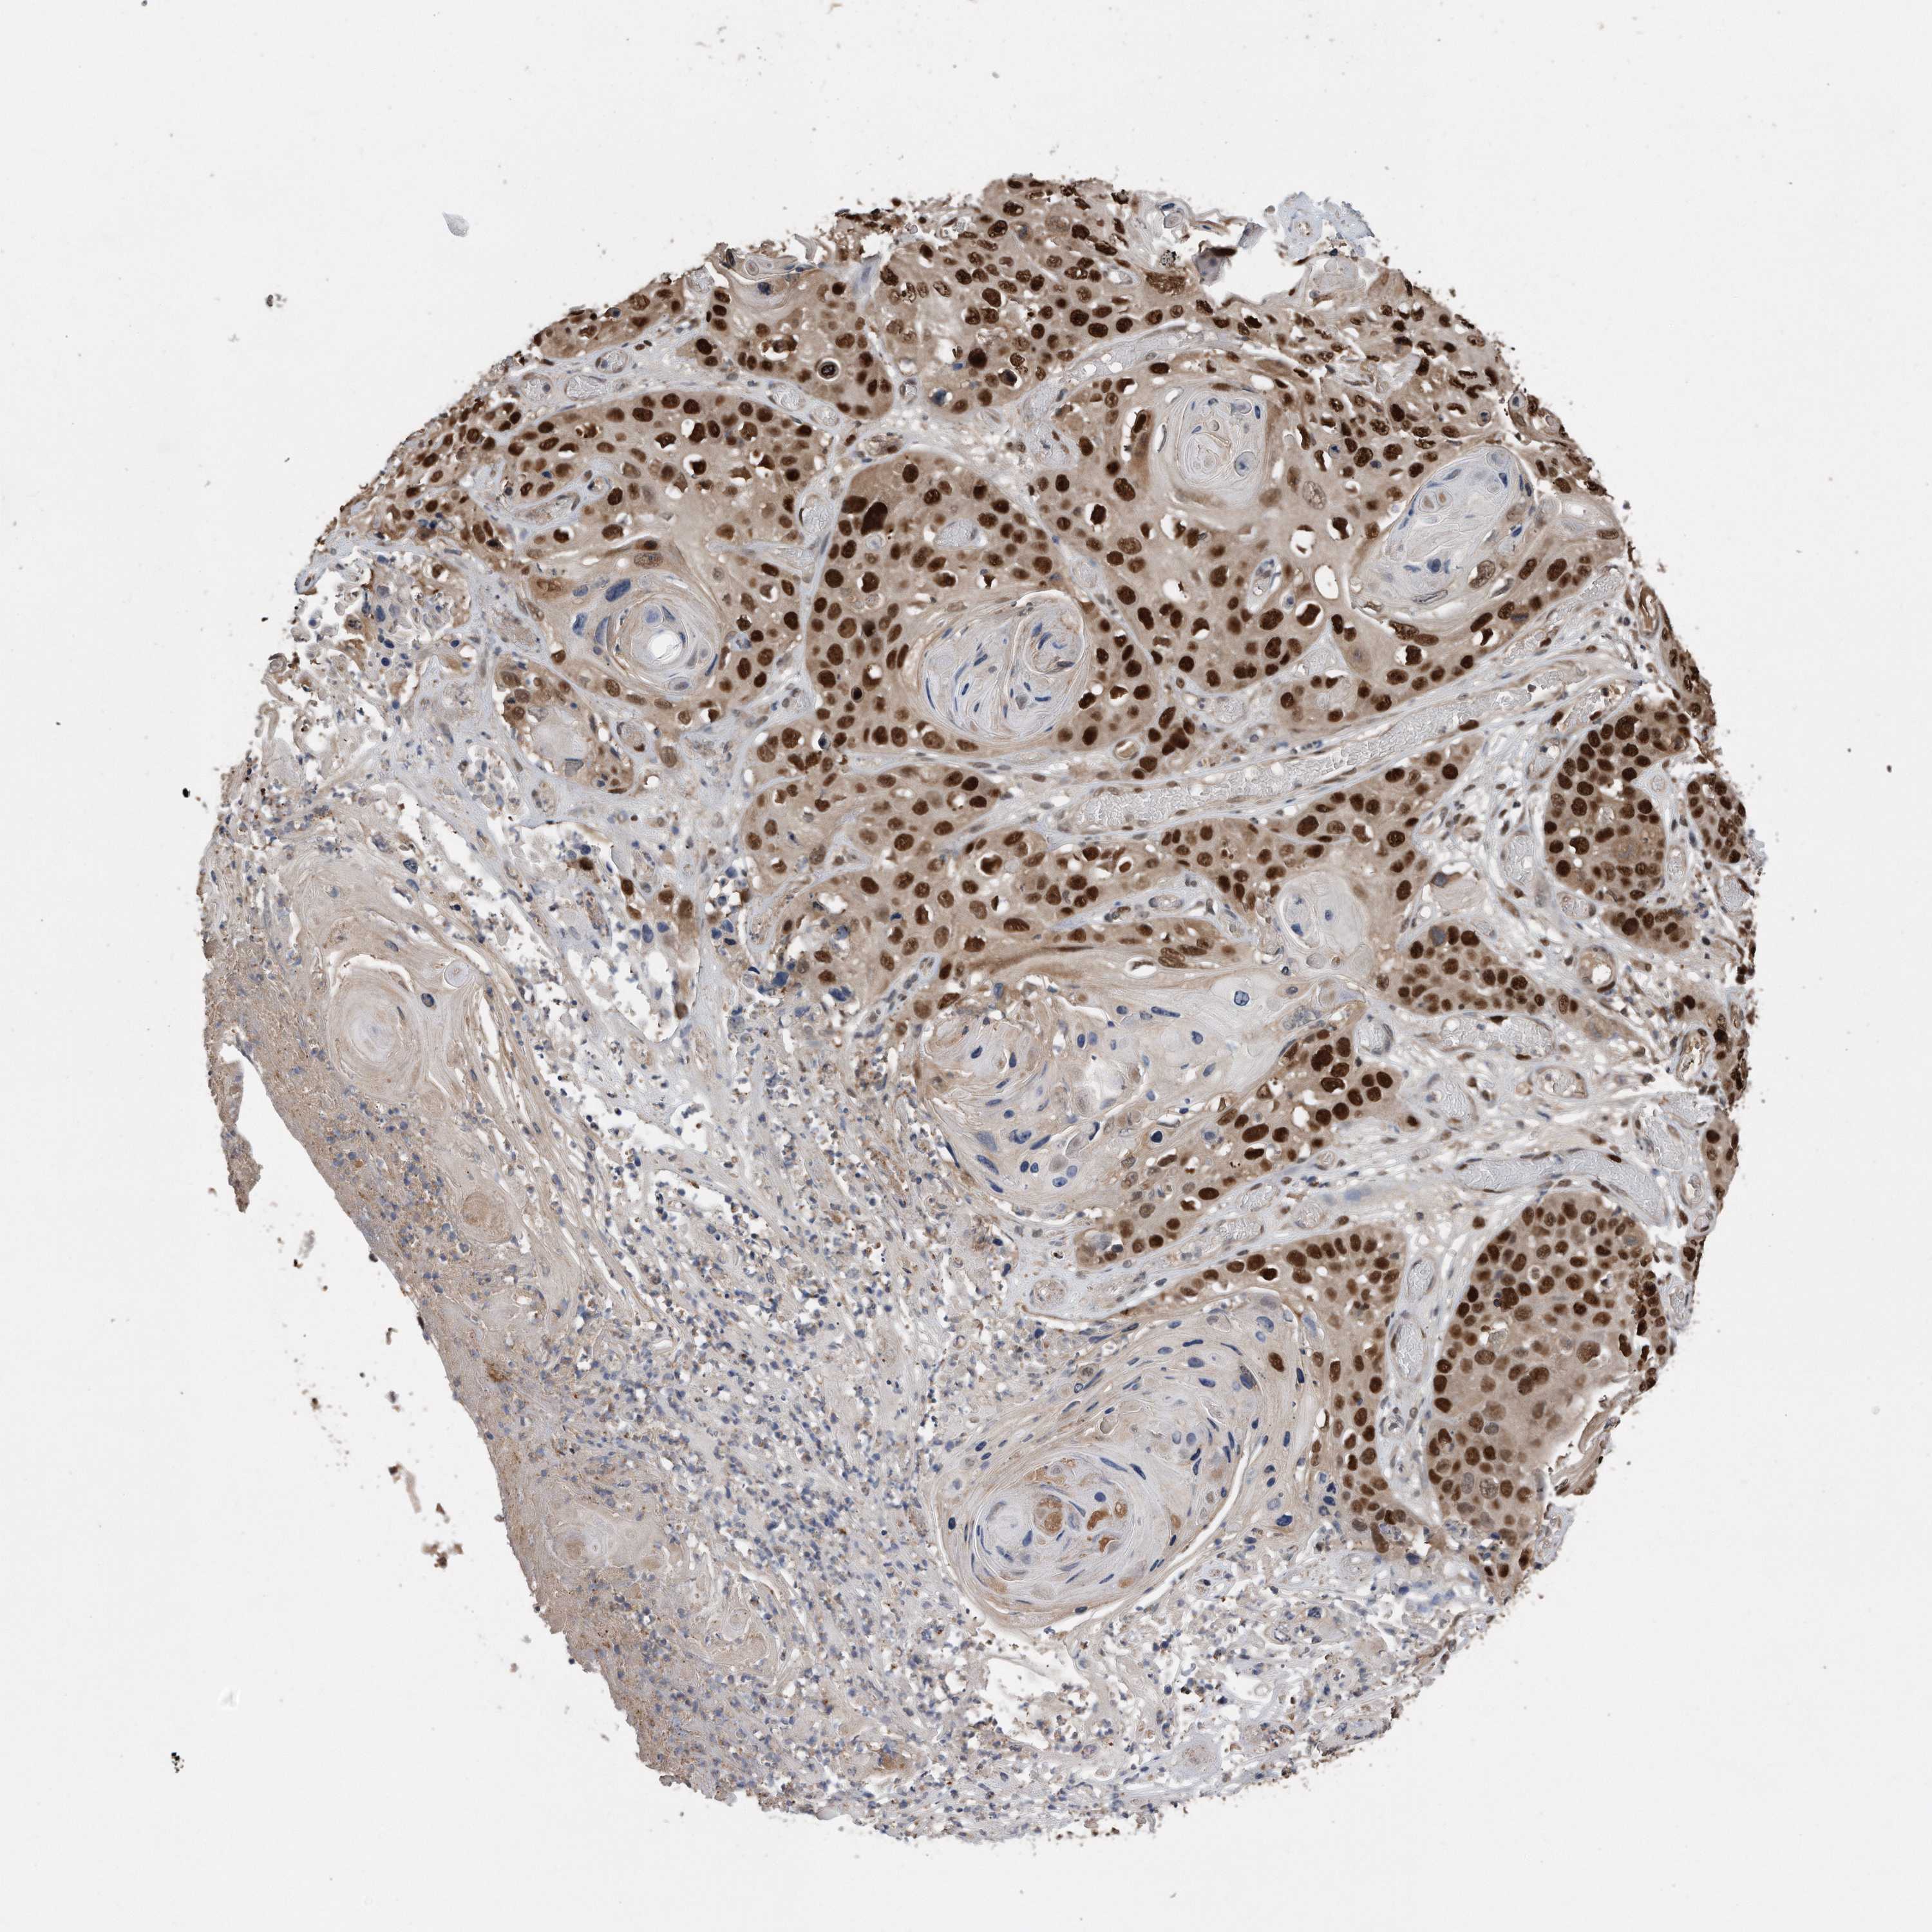

SKIN CANCER - Protein expressioni

A mouse-over function shows sample information and annotation data. Click on an image to view it in a full screen mode. Samples can be filtered based on level of antibody staining by selecting one or several of the following categories: high, medium, low and not detected. The assay and annotation is described here.

Each image is clickable and will lead to virtual microscopy that enables deeper exploration of all samples and also displays staining intensity scores, fraction scores and subcellular localization as well as patient and tissue information for each sample.

HPA030521

HPA030522

HPA030523

CAB000148

CAB080240

CAB080241

CAB080242

Staining

High

Medium

Low

Not detected

Intensity

Strong

Moderate

Weak

Negative

Quantity

>75%

75%-25%

<25%

None

Location

Nuclear

Cytoplasmic/membranous

Cytoplasmic/membranous,nuclear

Basal cell carcinoma

Squamous cell carcinoma, NOS

Squamous cell carcinoma, metastatic, NOS